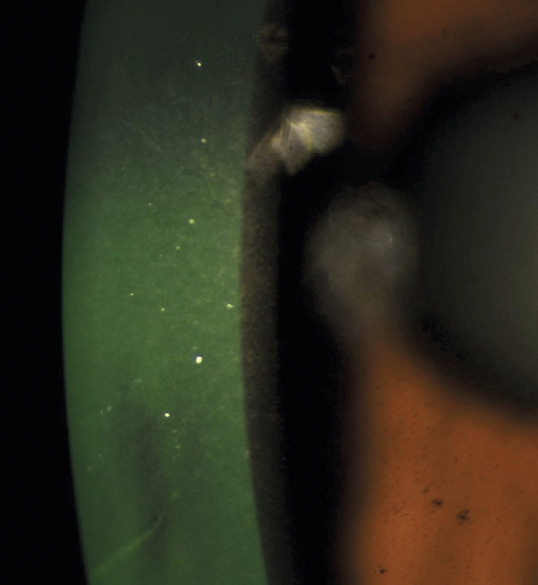

Bild 4: Fall 2 – Krukenberg-Spindel OU

Bild 5: Fall 2 – Zentmayer-Linie OS

A 46-year-old African American male presents for glaucoma quarterly monitoring. Medical history is positive for hypertension controlled with 50 mg hydrochlorothiazide and reports no diagnosis of diabetes mellitus or known drug allergies. Ocular history is positive for progressive myopia bilaterally and pigment dispersion syndrome converting to pigmentary glaucoma right eye mild, left eye moderate with treatment initiated in September of 2016. The pigmentary glaucoma was treated with 0.005% latanoprost in both eyes every evening. There was positive family history of glaucoma (patient’s father). Best corrected visual acuity was measured at 20/25 in each eye. Pupillary assessment revealed a stable 1+ afferent pupillary defect in the left eye. Confrontation fields were full to finger count in the right eye and superonasal constriction in the left eye. Extraocular motilities were full with no restrictions or report of diplopia in both eyes. Slit lamp examination is remarkable for a Krukenberg spindle (Figure 4) bilaterally and a Zentmeyer line (Figure 5) in the left eye. Intraocular pressures at 3:30 pm via GAT measured 18 mmHg right eye, 23 mmHg left eye. Gonioscopy was performed and revealed open angles to ciliary body with a concave iris configuration and 4+ trabecular meshwork pigmentation (Figure 6) and the posterior corneal surface. There was no pigment attached to the anterior lens surface. The highest recorded intraocular pressures prior to treatment were 27 mmHg right eye & 35 mmHg left eye. CCT measured 554 microns in the right eye and 538 microns left eye. Optic nerve head assessment revealed bilateral intact neuroretinal rims with vertical elongation greater in the left eye than the right with inferior neuroretinal rim thinning in the left eye (Figure 7).

Key features within all forms of pigment dispersion display areas of the anterior eye where pigment has either deposited or has been lost. These findings include mid peripheral iris trans-illumination defects in a spoke-like fashion, vertical deposition of pigment on the corneal endothelium known as Krukenberg spindles, a heavily pigmented TM observed on gonioscopy, pigment depositing on the posterior lens surface known as Zentmayer’s line and pigment settling at the junction of the zonules and posterior capsule termed Scheie’s stripe.34 More recently, the use of ultrasound biomicroscopy and anterior segment OCT has aided in the identification of concave iris configurations where it is not as readily apparent on slit lamp and gonioscopic evaluation alone.35